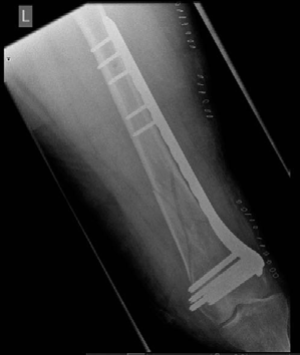

Minutes 3 and 4 EXAMINER : Okay, have a look at this radiograph and explain to me the technique the surgeon has used and what the principles are of this technique. (Figure 8.14.) CANDIDATE : The AP radiograph shows a multifragment distal diaphysis/metaphysis fracture that has been stabilized with a fixed-angle plate, using bridging plating the fracture zone has been bridged. Looking at the skin staples used to close the skin, I can infer that a closed indirect reduction and a less invasive technique was used. This technique was introduced to decrease soft tissue disruption and preserve blood supply. Length, alignment and rotation of bone was restored. Baumgaertel et ___al_. introduced the concept of biological plating and proved that indirect reduction and bridge plating was superior to direct fragment reduction and anatomical fixation in respect to bone healing.1

Figure 8.15 Anteroposterior (AP) radiograph right distal tibia with circular frame in situ. EXAMINER : Can you explain why the surgeon put screws on either ends of the plate and missed the middle? CANDIDATE : The surgeon intended to increase the working length of the implant (the distance between two points on either side of the fracture where the bone is fixed to plate or nail). This produces an even distribution of forces over a long segment and decreases stress at fracture and implant.